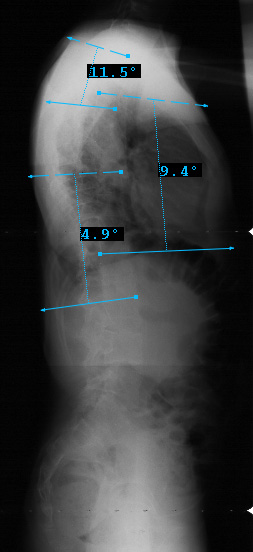

Preop LAT View